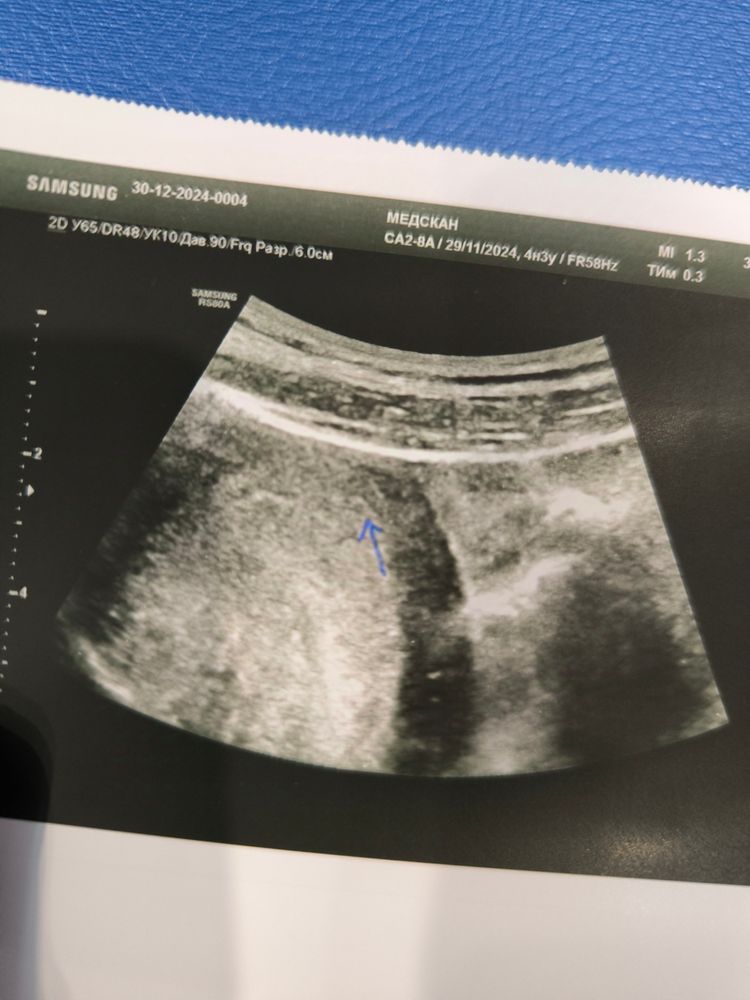

УЗИ 4 Нед 4 дня

Ксения , это 10 й день задержки

Боже, вы б ещё неделю назад пошли. Зачем так рано то? 30 дней это даже не 4 недели и 4 дня. А эмбриональные вообще двух недель нет. Конечно это точка может быть , что угодно, и внематочную вы в таком сроке не исключите.

Рано вы пошли. Хотя бы от 1500 на узи лучше идти.